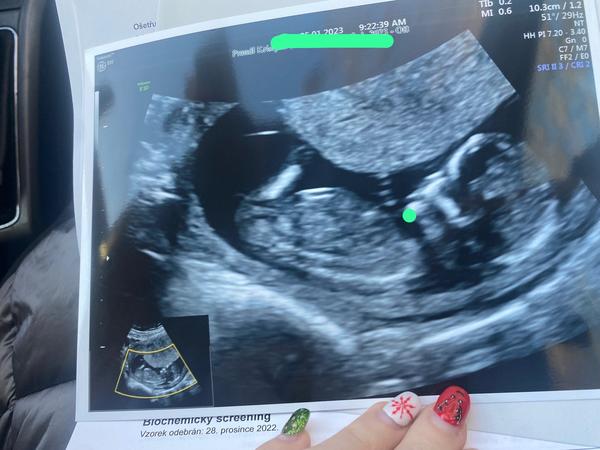

@krisstina93 a teď koukala a nic tam “netrčelo” proto mi rekla ze mam velkou naději naa holku

Tak jsem zvědavá 😄

@kristynaprandl myslím, že máme celkem podobný utz,že to holčička bude😊

@kristynaprandl vidím to i vás právě 😊😊mi máme nožky taky nahoru jen se to dobře zachytilo, ale u vás trochu zavazí víc, ale nemyslím si, že by to byl chlapeček 😊😊taky jsem moc chtěla holčičku, syna už mám a do třetího by jsme nešli určitě 🙈😅teda manžel 😊😊😅

@kar17 jee vy tam něco vidíte ? 🥰 mě přijde na te fotce jako by curalo😄😄😄takovej ocásek zaa zadeckem

@kristynaprandl myslím že tohle je ono, najděte si na fb theory Nub theory Queens já tam poslala utz správcům do soukromé zprávy a jsou fakt dobrý, fakt to poznají, mě dr napřed řekl 65%chlapečka, a podle jejich odhadu holčička a fakt ji mám už 2x potvrzenou 🙈🥰.

@kar17 tyto já FB nemám :( ale asi mate pravdu, druhy syn na stejném UTZ toto nemá 🤷🏻♀️

@kristynaprandl můj syn taky ne😊😊😊stojí to nahoru🤣🤣🤣😊😊tak držím palce, úplně chápu vaši touhu po holčičce 🙏❤️😊